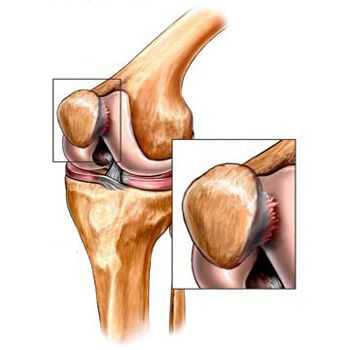

- травмы (переломы, разрыв менисков и передней крестообразной связки). [15][19] К сожалению, у любого человека, независимо от возраста, данные повреждения приводят к излишней нагрузке на хрящ. Перелом любых участков костей, покрытых хрящом, сопровождается образованием неровности — «ступеньки». [26] В этой зоне при движении происходит истирание, и формируется артроз;

Помимо внутреннего или наружного отдела колена артроз может поражать и поверхности между надколенником и межмыщелковой бороздой бедренной кости. Такой вариант называется пателло-феморальный артроз. [16]

Его причиной, как правило, становится подвывих, перелом или латерализация надколенника.

Артроз пателлофеморального сочленения

Пателлофеморальный остеоартроз - это повреждение хряща между коленной чашечкой и бедренной кости. В отличии от других типов ОА коленного сустава, которые возникают во внутренней (медиальной) и наружной (боковой) части колена и вызывают трудности при ходьбе по ровной поверхности, пателлофеморальный артроз провоцирует боль в передней части колена при сидении на корточках и подъема из сидячего положения. В этом случае отлично помогает коленный бандаж. По наблюдениям у пациентов, которые носили бандаж ежедневно, на МРТ было значительно меньше повреждений сустава и наблюдалось снижение боли в колене.